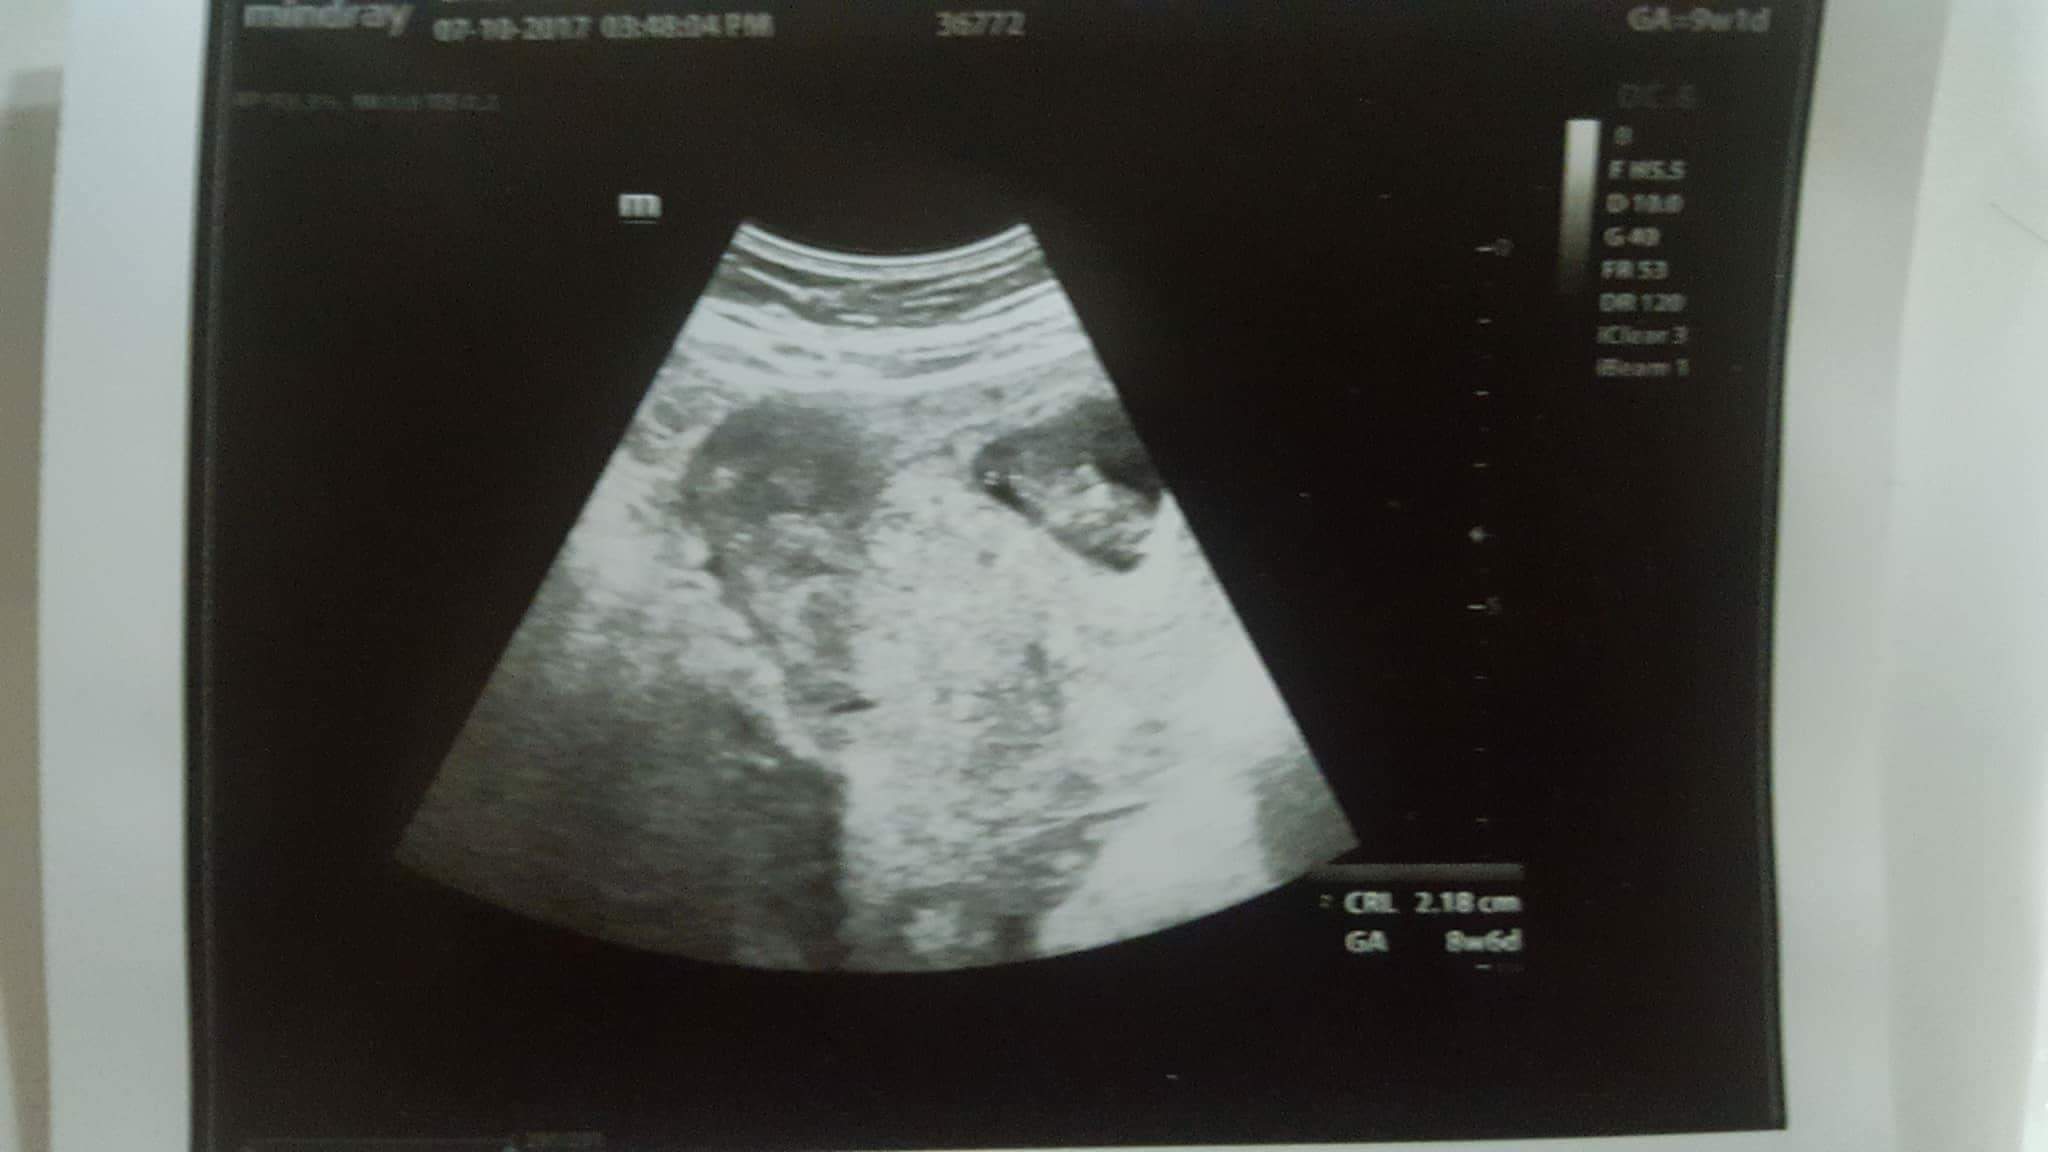

I am 9 weeks, had an ultrasound due to extreme dizziness and headache. Everything was fine.. baby was already moving, there was good heartbeat.

When I came home and showed ultrasound to my husband he pointed at second sac and asked me about it.. I don't know how I didn't notice it. My obgyn never said anything about twins. She did said there is no bleeding now! So it means second sac looking thing is not a blood. Wat is it? A hidden twin?

Attachment 37893